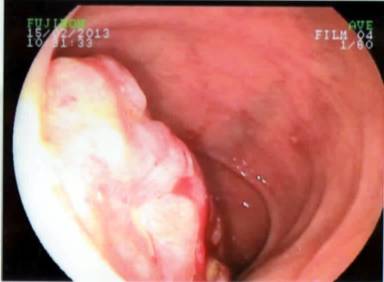

The patient had been on simvastatin the last five years, the rest of his medical history was negative. There was no relevant family or social history. In his physical examination, the patient was pale with no evidence of jaundice. The patient lost 10 kg during the past year without dieting and was suffering from symptoms of depression during the same period. An abdominal examination revealed an indirect left inguinal hernia. A rectal examination was normal. Investigations confirmed low haemoglobin 8.3 g/dL and haematocrit 25%.The rest of the biochemical examinations were normal. In the tumour markers, only the CA (carbohydrate antigen) 19-9 was elevated with a value of 169.67 U/mL. An abdominal ultrasound and colonoscopy showed non-pathological results. The gastroscopy revealed a large tumour of the ampulla of Vater (Figure 1), while the histology was positive for malignant cells with sarcomatous characters and frequent mitotic figures (>40/10 high power fields). The computed tomography scan demonstrated a large mass of the ampulla of Vater, causing obstruction and dilatation of the common bile duct, the intrahepatic and the pancreatic duct (Figure 2). The magnetic resonance revealed a large mass of the uncinate process of the pancreas of 4.7x4.5 cm and the dilatation of the intrahepatic bile ducts, common bile duct and pancreatic duct with no invasion of the superior mesenteric vessels or the portal vein and no metastasis.

Figure 1. Gastro-duodenoscopy demonstrating a tumor at the ampulla of Vater. |